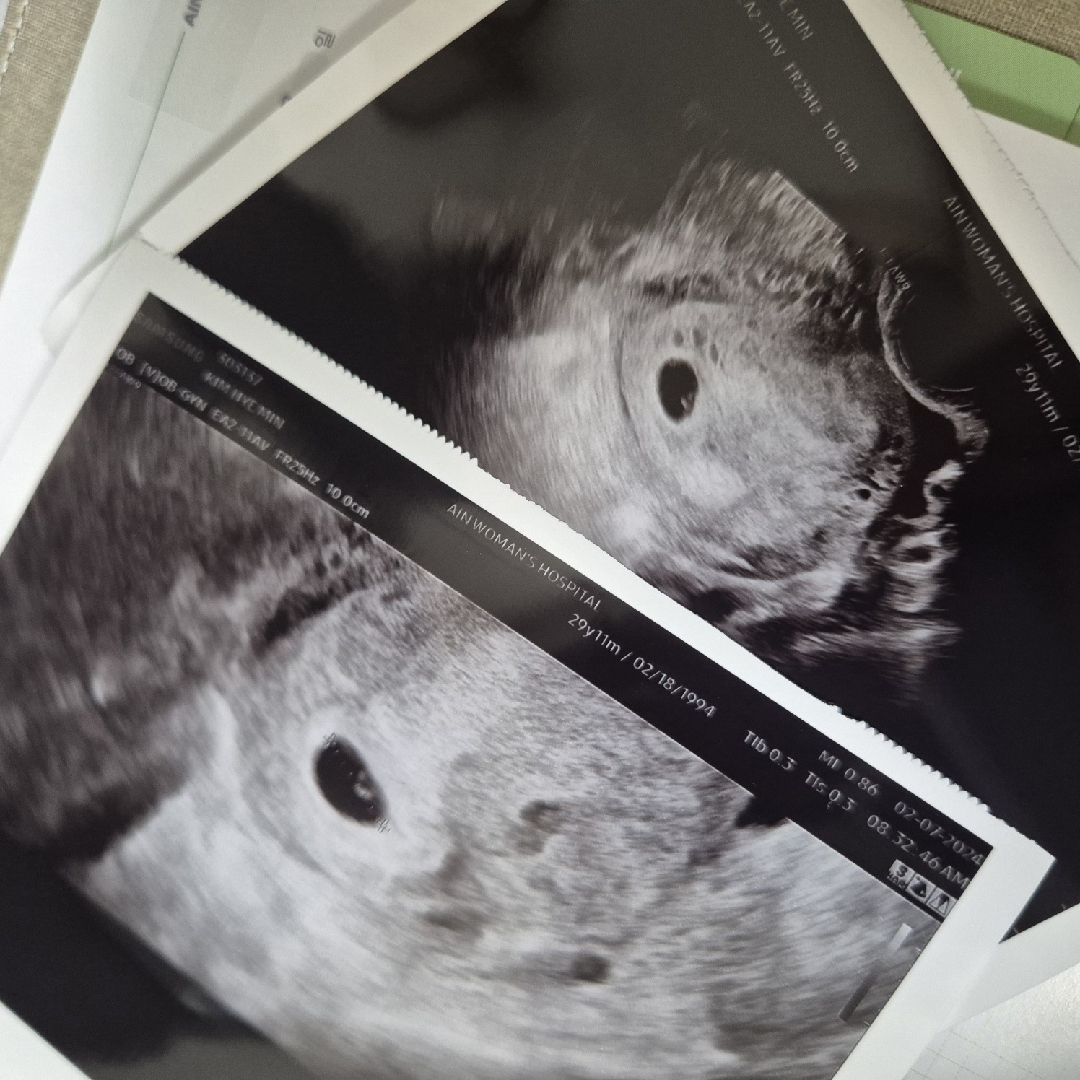

아기집 보고왔어요!!

정말 저번주에는 자궁벽이 두꺼워진것만 보아서 걱정했는데, 오늘 아기집에 난황까지 보고왔어요! 위치도 좋다고 해서 마음이 놓이네요ㅠㅠ

난황 너무 예뻐요! 저도 오늘 아기집만 봤는데 어서 난황도 보고싶어지네요🥹

감사합니다! 크기는 5주2일정도 된거같다고 들었어요!^^